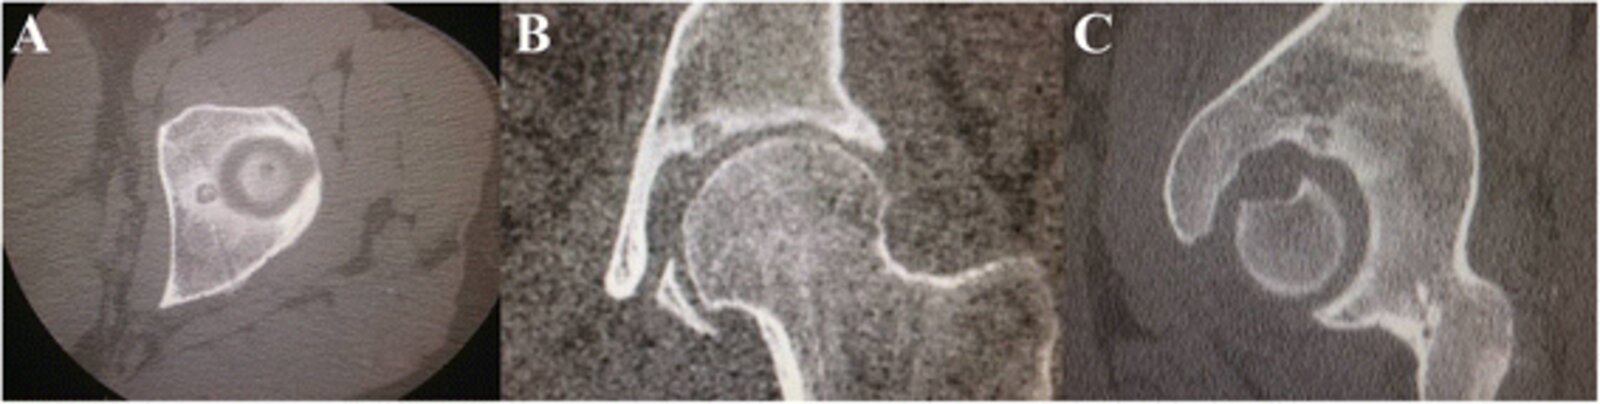

Osteoid osteoma [4]

• Description

• Small tumor (< 2 cm)

• Predominantly located in the cortex of long bones

• Epidemiology

• Peak incidence: 4–25 years [5]

• Sex: ♂ > ♀

• Clinical features

• Located in metaphysis and diaphysis of long bones (predominantly the proximalfemur, tibia, and humerus) and vertebrae

• Constant, intense pain that worsens at night

• Pain is responsive to NSAIDs (e.g., ibuprofen, aspirin)

• Diagnostics

• X-ray or CT: radiolucent core (osteoid), surrounded by perifocal sclerosis (nidus)

• Scintigraphy: usually intense enhancement

• Double-density sign

• Intraoperative nuclear imaging using a probe to detect the tumor

• Treatment: NSAIDs or surgical removal if pain is unresponsive to medical treatment